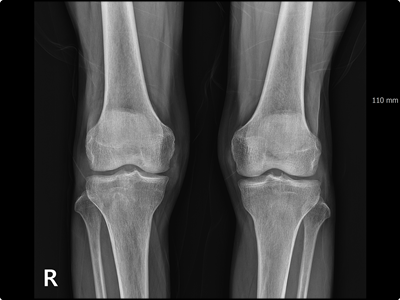

가장 일반적으로 나타나는 통풍 증상은 엄지 발가락, 무릎관절, 팔꿈치 등에서부터 염증이 시작되어 통증이 시작됩니다. 이러한 염증으로 인해 야기되는 통풍 증상은 여러가지가 있습니다.

보통 발목이나 발가락 혹은 무릎 그리고 손가락 등을 포함한 관절 부위에 염증으로 나타납니다. 또한 한번 시작된 통증 증상은 초기에 잠시 사라지는 것처럼 보입니다. 손가락 발가락 통풍 증상이 완화된 것으로 생각하기 쉽습니다. 하지만 몸의 컨디션이 좋지 않거나 면역력이 떨어지게 되면 다시 나타나는 경우가 대부분입니다. 그리고 빈번하게 나타나는 통증은 치료가 되지 않을 경우 관절염으로 굳어지기 쉽습니다.